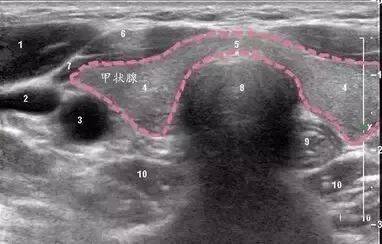

1:胸锁乳突肌;2:颈内静脉;3:颈总动脉;4:甲状腺左、右叶;5:甲状腺峡部;7:颈前肌肉(胸骨舌骨肌及胸骨甲状肌);8:气管;9:食管;10:左、右侧颈长肌。